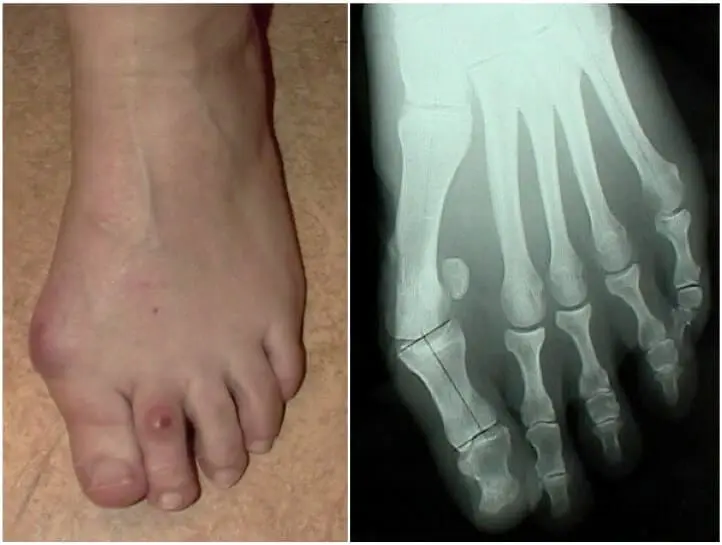

Le terme « hallux » fait référence au « gros orteil ». Dès que le gros orteil s’écarte de sa position axée vers le petit orteil, on parle d’une déformation en «valgus», d’où l’appellation habituelle d’hallux valgus. De part cela, il se développe inévitablement une tuméfaction osseuse à la partie interne du pied, appelée communément « bunion ou oignon ».

La plainte principale est donc le conflit de chaussage car le pied, et donc la « bosse », se retrouve dans un espace limité. Cela provoque un frottement, de l’inflammation et même parfois des plaies cutanées.